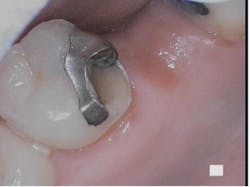

Fractured cusp

A fractured cusp becomes weakened and breaks off usually on its own. This is that fracture that breaks from eating soup or soft bread. The most common fractured cuspal areas are the cusps on the tongue side on the lower back teeth and on the cheek side of the upper back teeth (figure 2). It rarely damages the pulp and doesn’t cause much pain.

A fractured cusp occurs when weakening of the cusp happens through prolonged excessive force or severe tooth decay. Common forces to cause a fractured cusp are, chronic grinding and clenching, trauma, failed restorations, and biting into hard foods. Symptoms may be pain upon compressions and/or pain from the release of biting pressure. More symptoms may be temperature sensitivity, sharp pain when chewing, gum irritation, and a sharp edge on the tooth—frequently noticed by the tongue.

Treatment with these fractures is commonly a crown, with its purpose to cover and protect the tooth. A filling in some cases may be advisable depending on the amount of tooth fractured. If the fracture is deep into the tooth a root canal, will help to restore the tooth. If a fracture is detected early, before the tooth breaks, an onlay may be placed over the cracked cusp. 2